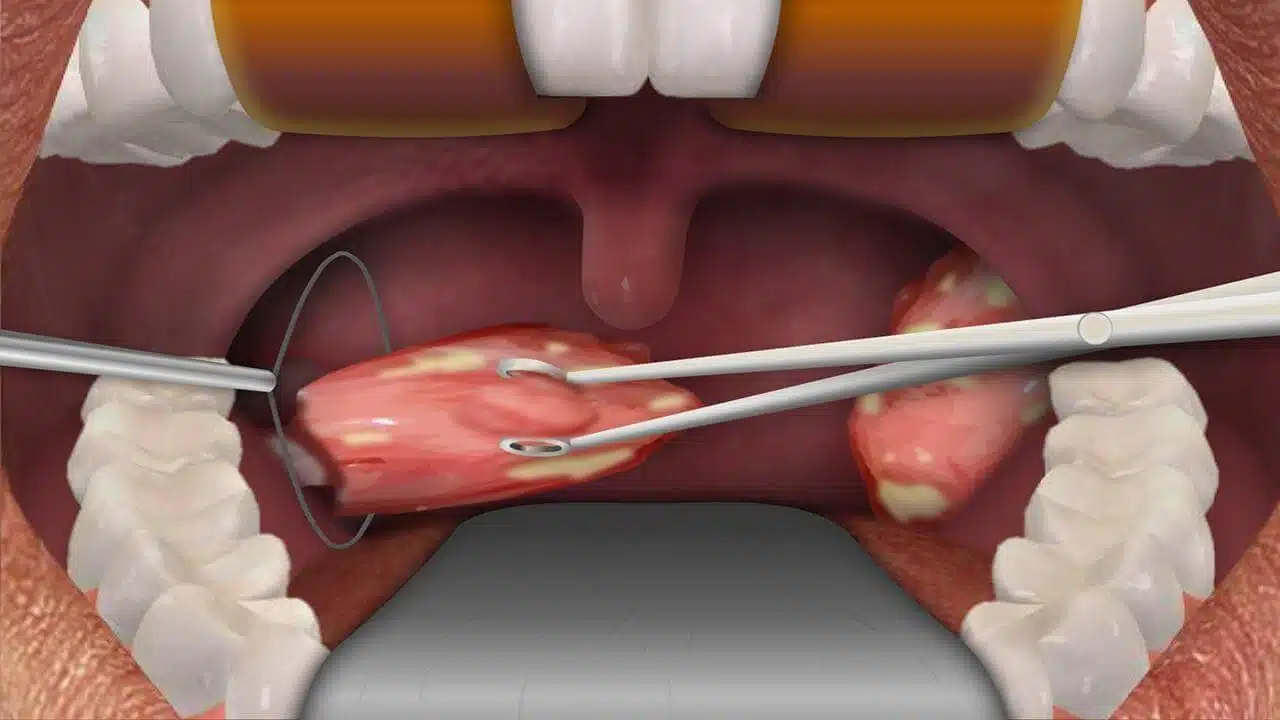

The procedure is done under general anesthesia, so the child is given a mixture of gas and an intravenous medication. He/she will be continuously monitored by a pulse oximeter and heart rate monitor. There will be no external incisions. When the anesthetic takes effect the doctor cuts the tonsils with a surgical blade and removes them through the mouth. Then she/he burns (cauterize) the base with an electrical cauterizing unit. This procedure takes less than 60 minutes.